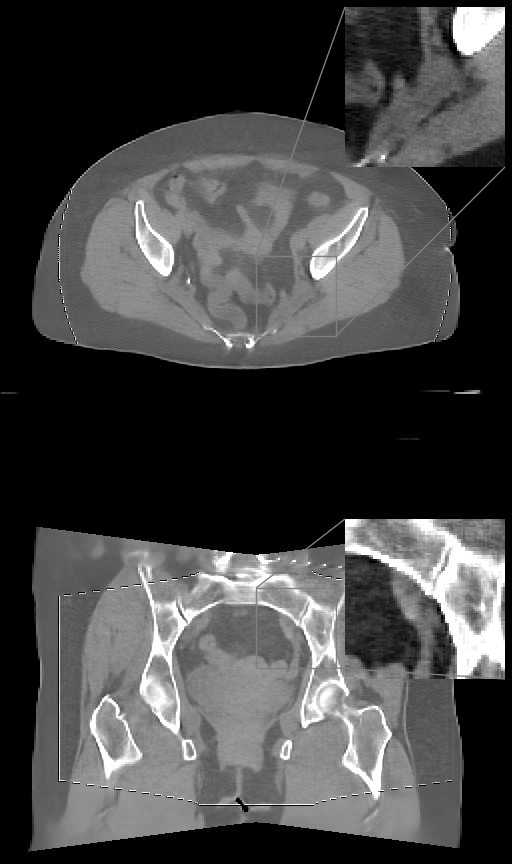

Refer to caption

(a)

(b)

(c)

(d)

Figure 2: (a) Axial (top) and coronal (bottom) slices of thorax CT, HU range=(-1000, 800) and (-150, 250) for ROI, (b) U-net (c) \partialU-net, (d) LIRE++

We perform extensive evaluation of LIRE++ and the baselines using image quality metrics such as PSNR and SSIM, which are computed for attenuation values, as well as MAE in Hounsfield Units due its importance for radiotherapy applications.

In Table 1 we report these metrics on the thorax & pelvic test set, and the corresponding box plots are provided in Figure 1. All metrics are computed for the full field of view region, i.e., the voxels which are present in at least half of the projections, which coincides with the field of view given by FDK and TV methods. Table 1 also contains mean total inference times per volume on NVIDIA A100 accelerator and the parameter counts, where in case of FDK and TV the parameter count of scatter pre-correction U-net is provided. In case of TV reconstruction, high inference time is partially due to multiple CPU-GPU memory transfers in ODL. Examples of thorax image slices of a ground truth image and the corresponding reconstructions from baselines and LIRE++ are presented in Fig. 2. Similarly, pelvic & abdominal image slices are presented in Fig. 3. The image samples demonstrate particularly well that LIRE++ is superior in reproduction of these soft tissue details which appear blurred in the baselines. Field-of-view in the reconstructions given by LIRE++ and \partialU-net is increased since the training loss is optimized over all voxels which are present in at least one projection. Extended FoV reconstruction quality for the voxels which are observed in at least one projection, but less than half of all projections, is slightly higher in LIRE++ reconstructions compared to \partialU-Net by appoximately 1 dB higher PSNR.